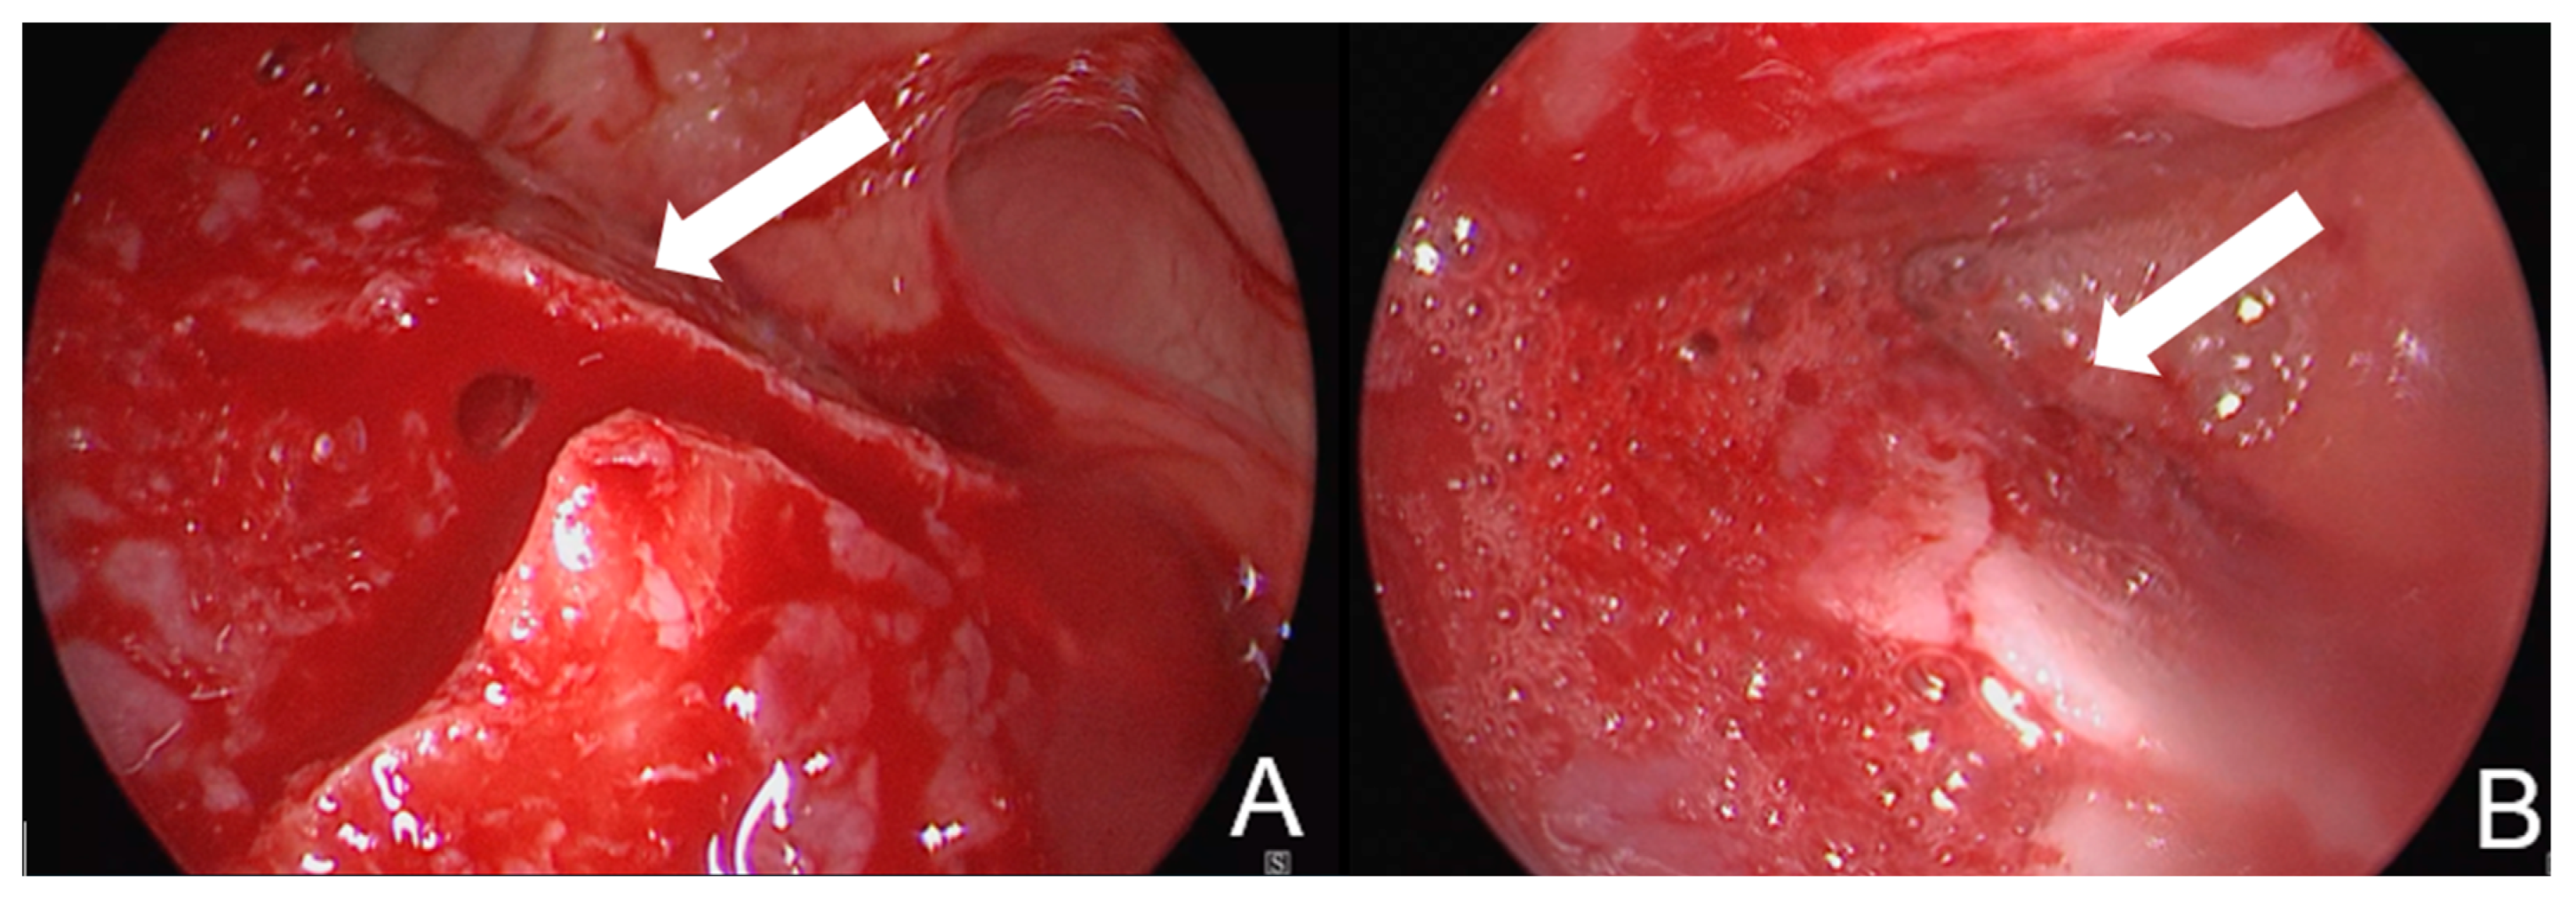

A 2.7 mm 30° endoscope is inserted through the bony window to access the frontal sinus. This allows for direct visualization of the fracture prior to reduction. The fracture is then reduced using a small, rigid instrument such as an LPRF plugger or urethral dilator. Following reduction, the outcome is assessed both endoscopically and by manual palpation (Figure 2). If possible, a perioperative CBCT was taken to verify the reduction in the frontal sinus. In other cases, if no CBCT could be taken perioperatively, a control CT scan was made within 1 week after the procedure.

Figure 2. (A) Image of the fracture of the anterior wall of the frontal sinus before reduction; (B) image of the fracture of the anterior wall after reduction in the same patient. The anterior wall of the sinus is located at the bottom of the image. The fracture line is indicated with an arrow in both images.